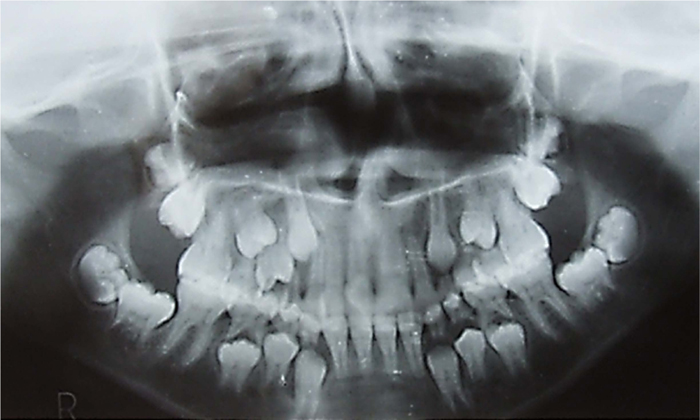

Upon clinical and radiographical examinations, dental findings were as follows: a unilateral, large, wide permanent maxillary left central incisor crown with a notch in the incisal edge. Radiographically, a single large pulp chamber and a single incomplete root formation were observed. All of these data came under the gemination dental anomaly. Moreover, two identical permanent maxillary lateral incisors were present on the right side, indicating a supplemental supernumerary lateral incisor. Teeth were vital, and overcrowding in the maxillary anterior teeth region was observed (Fig. 1a). Besides, the girl was still in mixed dentition and suffered from multiple dental caries due to poor oral hygiene.

The clinical intraoral examination, including inspection, palpation, vitality testing, and periodontal probing, was performed for the upper anterior teeth and surrounding tissues to determine the child's oral hygiene. Moreover, the radiographic examination included a panorama and two periapical radiographs to confirm the presence of geminated and supplemental teeth (Figs. 2a–b and 3a–b).

The diagnosis for this case is made on the basis of the history taken and adequate clinical and radiographical examinations. Clinically, the maxillary teeth count is increased despite the left questionable tooth being diagnosed as a gemination. This count increases because of two maxillary right lateral incisors, leading to abnormal teeth count [4, 17]. A radiographical examination by using a periapical radiograph in the incisor region besides a panorama radiograph has been considered as one of the conforming and effective methods to detect gemination and supernumerary teeth [7, 20, 21].